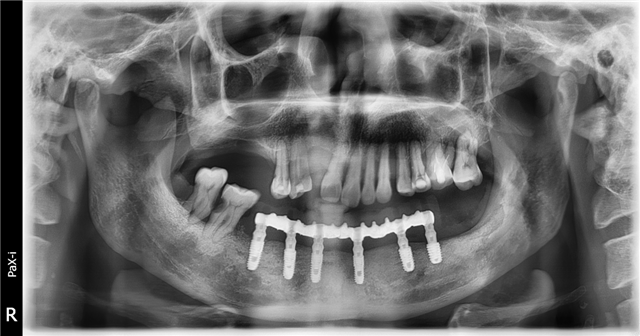

2021年4月,一位来自广州天河区的60多岁老人前来德伦寻求帮助。他自述在其他医院种牙失败,种了六颗牙,现在掉了四颗,感觉自己在种牙上花了很多冤枉钱和时间,走了很多弯路,精疲力尽,受罪不说还赔上了健康。

患者来到德伦口腔,接待他的是德伦口腔东风总院种植科罗朝阳副主任。经过罗主任对患者全身状态评估,口内状况及影像数据的检查,告知患者符合再种植条件,并给出了多种种植修复方案,患者知情同意,选择数字化导板种植,埋入愈合,3个月后二期修复,咬合重建,金塑桥过度,最终钛支架和烤瓷牙固定种植义齿修复方案,帮助患者恢复口腔功能及身体健康。